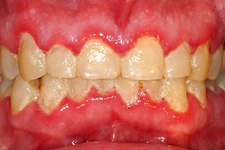

Diş Ekiminden Sonra Bakım Süreci

Diş ekiminden sonra bakım süreci oldukça önemlidir. İşte dikkat edilmesi gereken bazı noktalar:

- Ağız Hijyeni: İşlem sonrası ağız hijyenine özen göstermek enfeksiyon riskini azaltır. Ancak, işlem bölgesine doğrudan zarar vermemek için nazik davranmak gerekir.

- Beslenme: İlk günlerde yumuşak ve sıvı gıdalar tüketmek, iyileşme sürecini kolaylaştırır.

- Kontrol Randevuları: Doktorun önerdiği kontrol randevularına zamanında gitmek, sürecin sağlıklı ilerlemesini sağlar.

Kendi deneyimim olarak, diş ekimi sonrasında dikkatli bir bakım süreci geçirerek enfeksiyon problemi yaşamamıştım. Ama her bireyin iyileşme süreci farklı olduğu için, bireysel durumunuza uygun önerileri hekimden almak en doğrusudur.